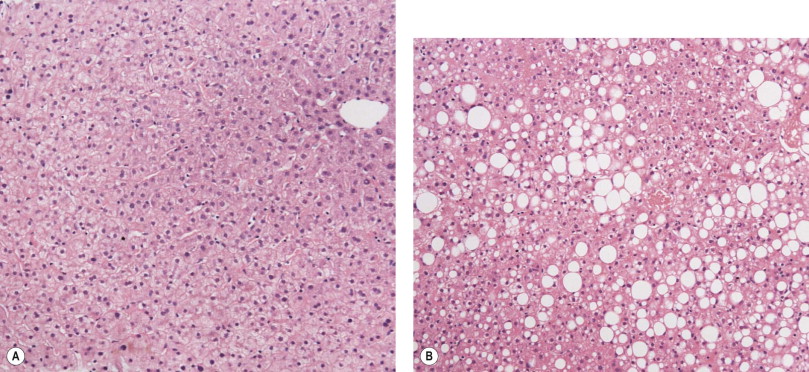

Stéatose hépatique

3-s2.0-B9780702031311000080-f008-003ab-9780702031311.jpg